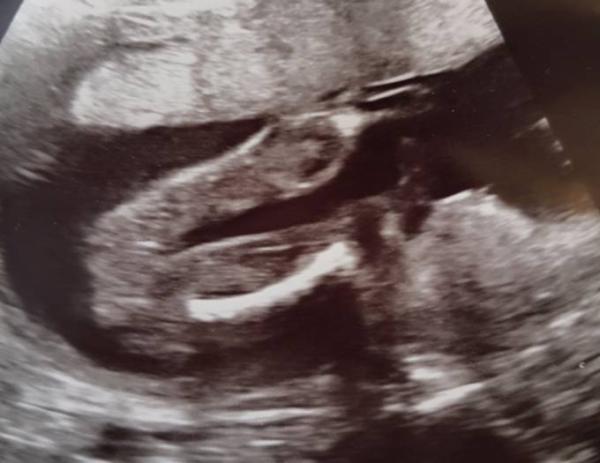

Heute hat sich das Baby mal ganz toll gezeigt. Mein FA hat extra sogar mittendrin noch 3x geschaut um absolut sicher zu gehen. Wir bekommen unsere 3. Prinzessin. Die ist jetzt schon 450g schwer und 25cm lang. Anbei noch Bildchen. Hach bin ich glücklich. Alles zeitgerecht entwickelt und Top fit. In 4 Wochen haben wir dann die Feindiagnostik.

Bild zu Outing endlich eindeutig - Forum für Februar - Mamis

Wow das ist ja ein richtes Portrait Foto :) Wie hübsch die kleine! Herzlichen Glückwunsch!